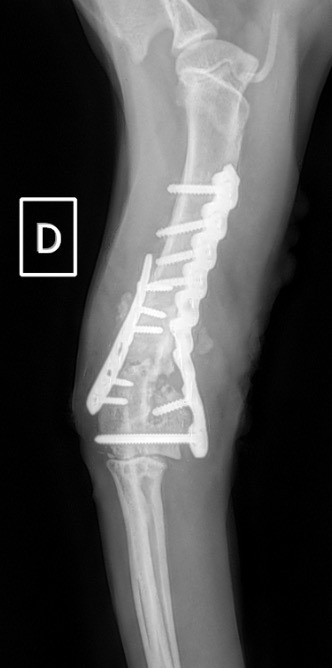

Notre préférence va vers le placement de deux plaques humérales : une médiale de la plus grande taille possible et l’autre latérale, généralement d’une taille inférieure à la première. Dans l’exemple 1 (chat européen), une plaque de 2 mm est utilisée médialement et une plaque de 1,5 mm latéralement. Dans l’exemple 2 (chien Malinois), une plaque de 3,5 mm est utilisée médialement et une plaque de 2,7 mm latéralement.

Figure 5 : Post-Op Immédiat

Figure 6 : Post-Op 1 mois

Figure 7 : Post-Op 2 mois